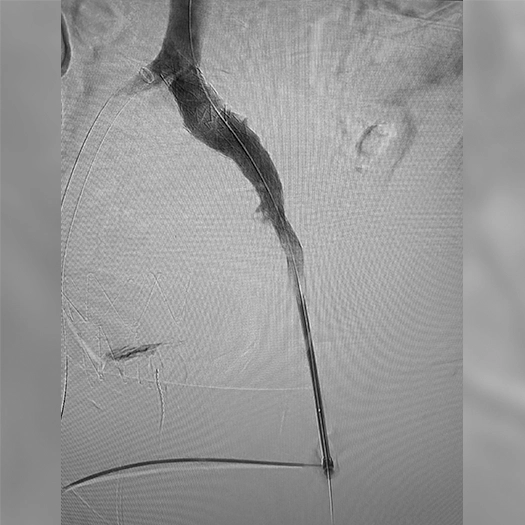

Venous Cases

Images used with permission and provided for illustrative purposes only. Procedural techniques and decisions based on physician’s medical judgment. Individual results may vary. Consents on file at Penumbra, Inc.